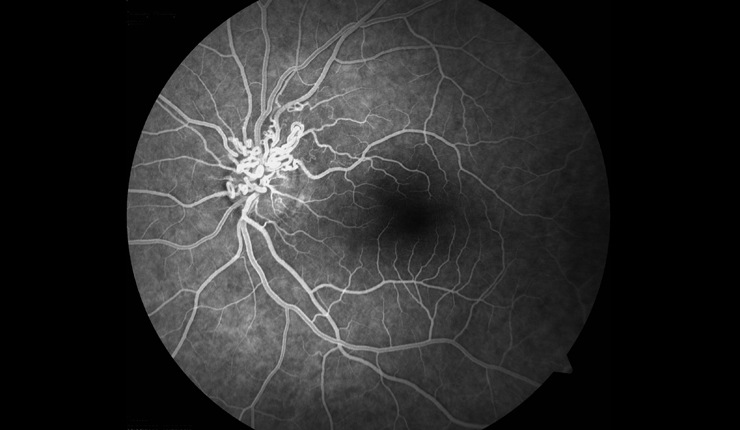

3D OCT of retinal angiomatous proliferation (RAP) showing news vessels tracking through the retina and associated intra-retinal oedema.